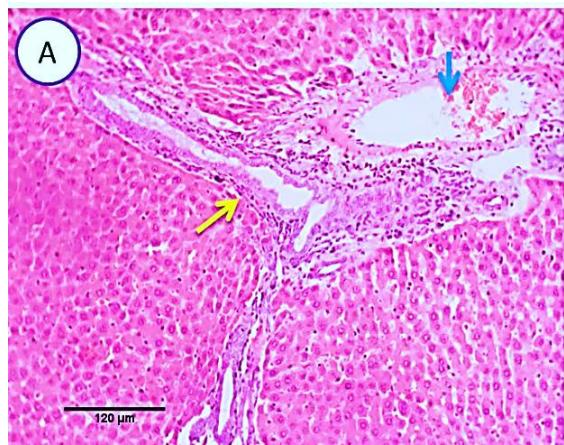

Fig. 3: Photo-micrograph from liver, group (2), showing, portal biliary proliferation (yellow arrow), congestions of portal blood vessels (blue arrow) and round cell infiltration beside degenerative changes in a few hepatocytes. Scale bars 120, 20 um.

Liver: Examined sections from liver of this group denoted moderate portal biliary proliferation, congestion of portal blood vessels, round cell infiltration, multifocal interstitial lymphocytic and macrophages aggregations replacing previous necrotic patches beside degenerative changes in a few hepatocytes. (Fig.4).